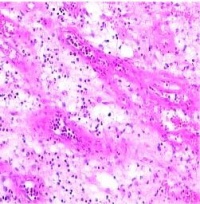

肉芽组织(granulation tissue):由新生薄壁的毛细血管以及增生成纤维细胞构成,并伴有炎性细胞浸润,肉眼表现为鲜红色,颗粒状,柔软湿润,形似鲜嫩的肉芽故而得名。为幼稚阶段的纤维结缔组织.

镜下可见大量由内皮细胞增生形成的实性细胞索及扩张的毛细血管,向创面垂直生长,并以小动脉为轴心,在周围形成袢状弯曲的毛细血管网。在毛细血管周围有许多新生的纤维母细胞,此外常有大量渗出液及炎性细胞。炎性细胞中常以巨噬细胞为主,也有多少不等的中性粒细胞淋巴细胞,因此肉芽组织具有抗感染功能。巨噬细胞能分泌PDGF、FGF、TGF-β、IL-1及TNF,加上创面凝血血小板释放的PDGF,进一步刺激纤维母细胞及毛细血管增生。巨噬细胞及中性粒细胞能吞噬细菌及组织碎片,这些细胞破坏后释放出各种蛋白水解酶,能分解坏死组织及纤维蛋白,肉芽组织中毛细血管内皮细胞亦有吞噬能力,并有强的纤维蛋白溶解作用。

2.镜下观察 基本结构为:①大量新生的毛细血管,平行排列,均与表面相垂直,并在近表面处互相吻合形成弓状突起,肉眼呈鲜红色细颗粒状。②新增生的纤维母细胞散在分布于毛细血管网络之间,很少有胶原纤维形成。③多少不等的炎性细胞浸润于肉芽组织之中。肉芽组织内常含一定量的水肿液,但不含神经纤维,故无疼痛。